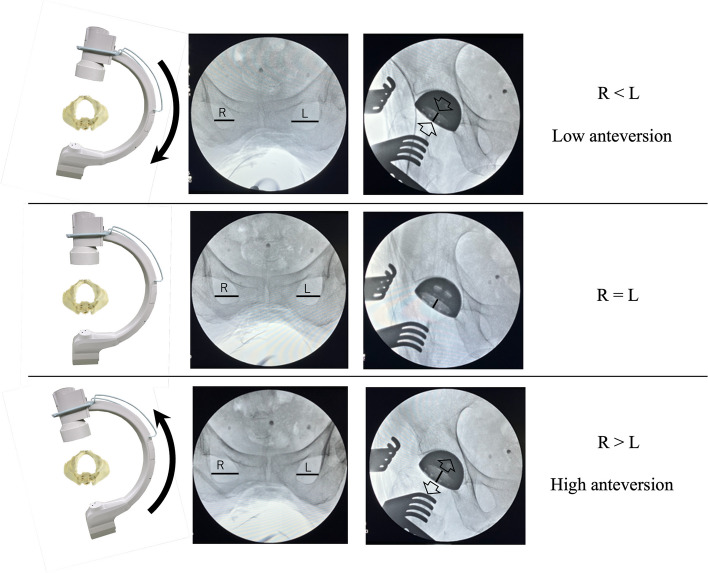

Methods: This retrospective study included 101 patients who received primary THA via the direct anterior approach using a conventional traction table with fluoroscopy between July 2022 and October 2024. Two observers evaluated radiological outcomes using postoperative anteroposterior X-rays. The intraclass correlation coefficients of cup positioning angles were calculated (inclination: 0.92, anteversion: 0.89 for intra-observer agreement; inclination: 0.91, anteversion: 0.85 for inter-observer agreement). Complications were defined as dislocation, periprosthetic fracture, ankle fracture, implant loosening, nerve injury, surgical site infection, deep vein thrombosis, and revision surgery for any reason.

Results: Radiographic analysis showed an average cup inclination of 38.1° ± 4.1° (99.0% within Lewinnek's safe zone). The average cup anteversion was 12.0° ± 4.7° (97.0% within Lewinnek's safe zone). None of the patients experienced any complications.